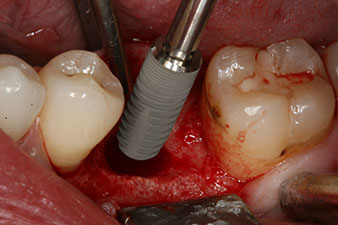

Abb. 1: Klinische Ausgangslage nach Abheilung der Extraktionsalveole 36: Die Knochenbasis ist breit und es ist genügend keratinisierte Gingiva vorhanden.

Bei einem 28-jährigen Patienten mit ausgeprägter Raucheranamnese musste Zahn 36 als Folge einer rezidivierenden apikalen Parodontitis extrahiert werden.

Wegen der weitgehend intakten Nachbarzähne kam als Lückenversorgung nur ein Implantat in Frage.